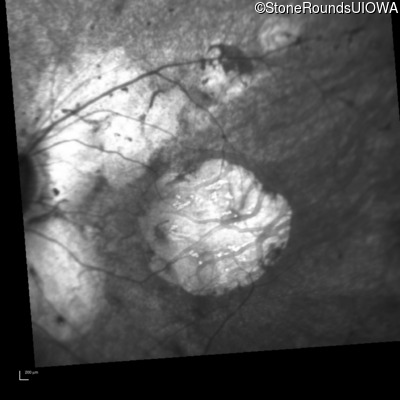

Infrared Fundus Photograph - Right - 20/100 -1

Exemplar